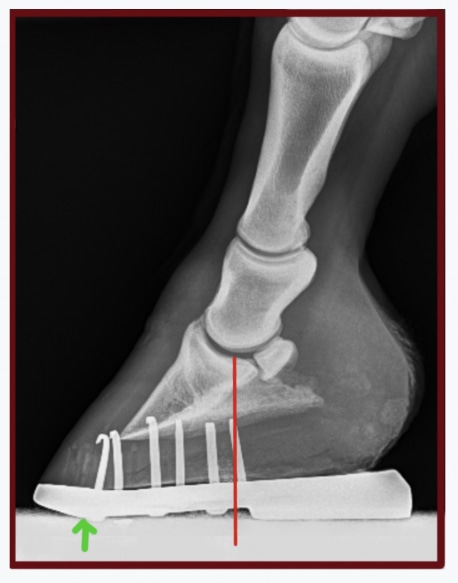

The position of this similar shoe, with more wedge and improved center of rotation has been moved back. Red line indicates center of rotation of the coffin joint, green arrow indicates breakover.